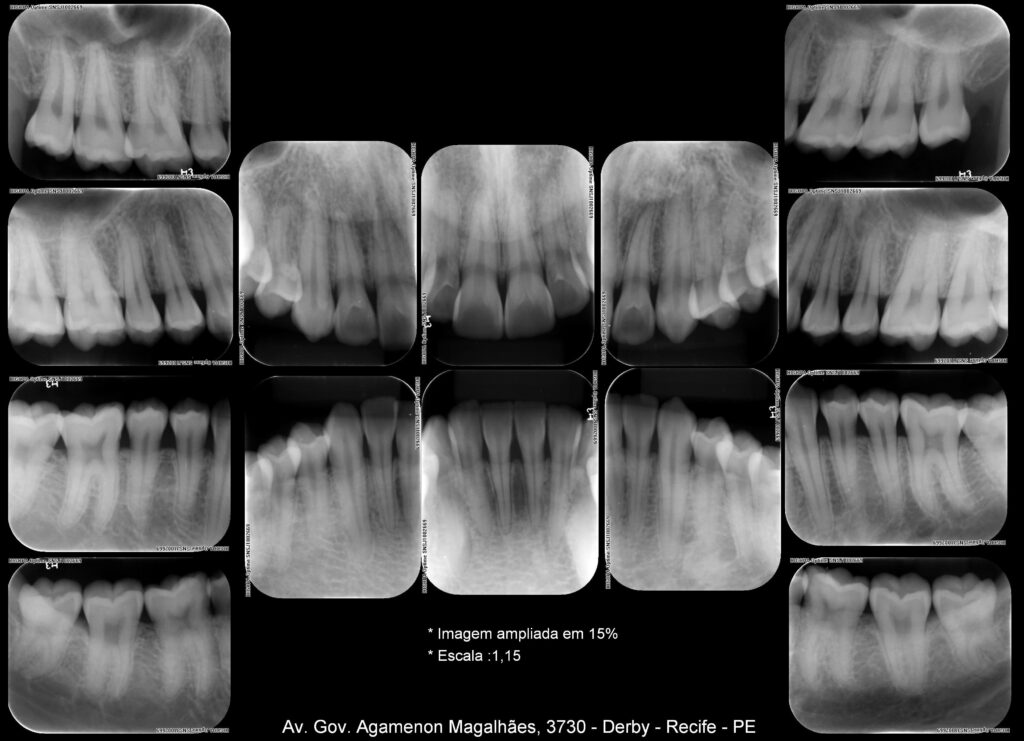

Radiografias Digitais

Periapicais

Interproximais